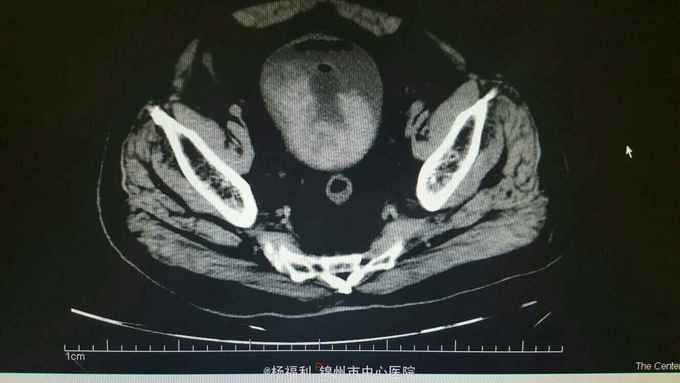

膀胱造瘘管内血尿伴血块,造瘘管周围窦口新鲜肉芽形成。耻骨上隆起,压痛阳性,扣诊浊音。 盆腔ct:见影像资料。内见大量血块。

尿潴留。膀胱内出血。膀胱造瘘术后。 给与患者留置尿管后行膀胱持续冲洗,血尿持续,于膀胱镜下给与患者清除膀胱内血块,发现造瘘口周围膀胱壁出血,滤泡样隆起,病理回报轻度不典型增生。电凝止血后回病房。